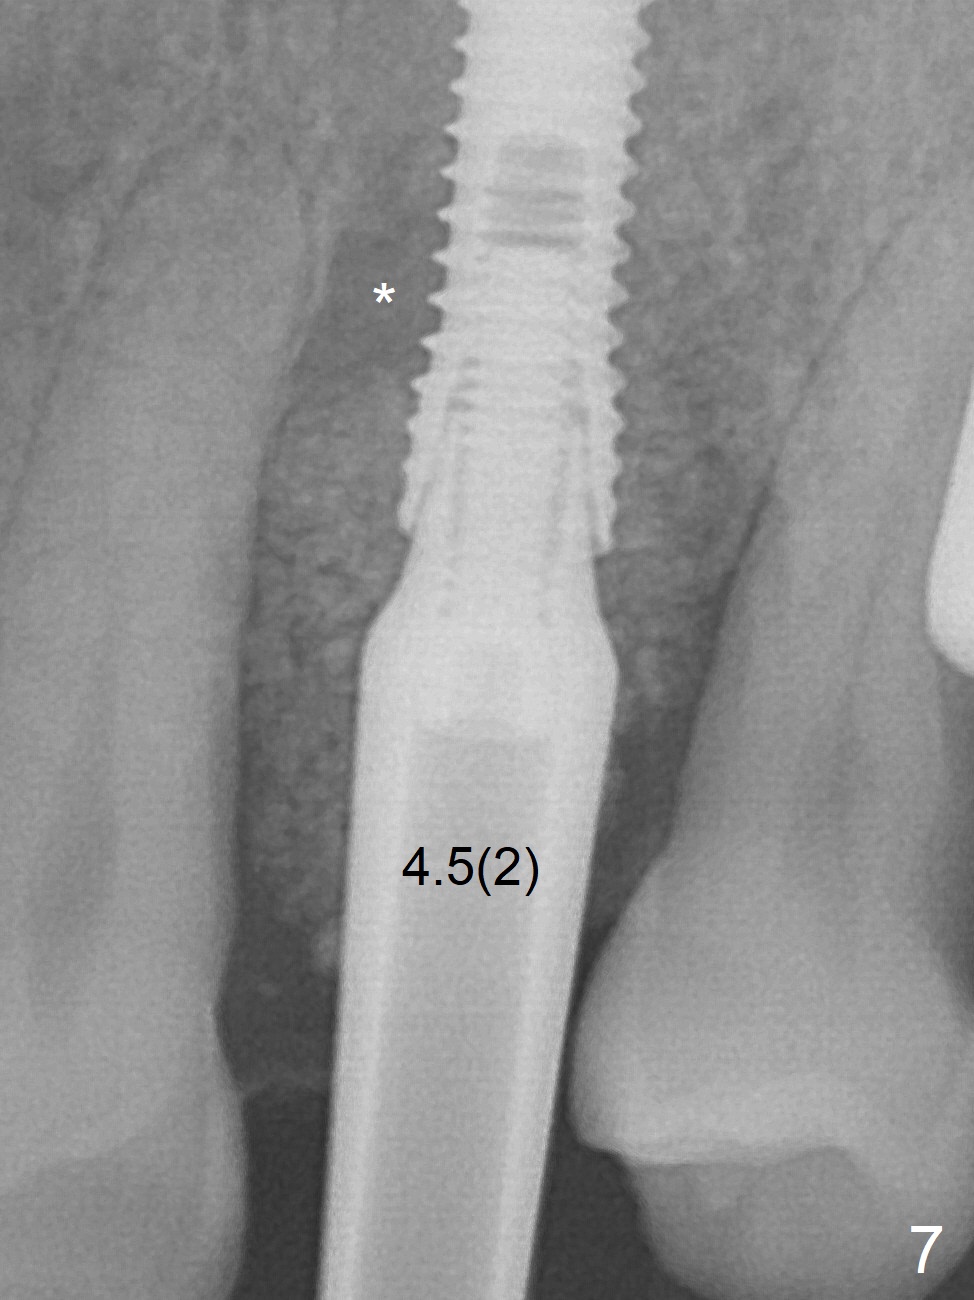

A few days prior to surgery, the tooth #12 developed abscess, self controlled by water pik (Fig.1 *). The buccal plate is defective. Initial osteotomy is close to the root of the tooth #11 (Fig.2). After adjustment of the trajectory and the depth of osteotomy (Fig.3), a 3.8x15 mm dummy implant is placed (Fig.4,5). In spite of a shorter implant (3.8x13 mm) placed deeper, approximately 7 mm implant threads are not covered buccally by the native bone (Fig.6 red dashed line). If the implant were placed deeper, the crown/implant ratio would become more unfavorable (abutment screw loosening, Fig.7). Since a mill abutment (4.5(2) mm) is inserted before Vanilla Graft, the deepest portion of the socket is unfilled (Fig.7 *). With meticulous use of a long explorer and additional allograft, the space is closed (Fig.8 *). The buccal plate collapses with apparently fistula formation 2 months postop. The patient removes the provisional for cleaning. It appears that the mill abutment is buccally placed and needs heavy reduction. The mill abutment is loose 2 months 10 days postop. When it is retightened, it tilts distal. Bone remains around the implant 6 months postop (Fig.9). Without a provisional at #12 for 5 months, the tooth #13 appears to have been shifted mesially (Fig.10 arrow). The mill abutment at #12 changes to a healing one. A lingual button is placed in the mesial surface of #13. Splinted provisional is fabricated with supraocclusion at #14 and 15 as an anchor (implants). The tooth #13 is being distalized with power chains. Limited ortho is finished nearly 2 months post banding (Fig.15,16).